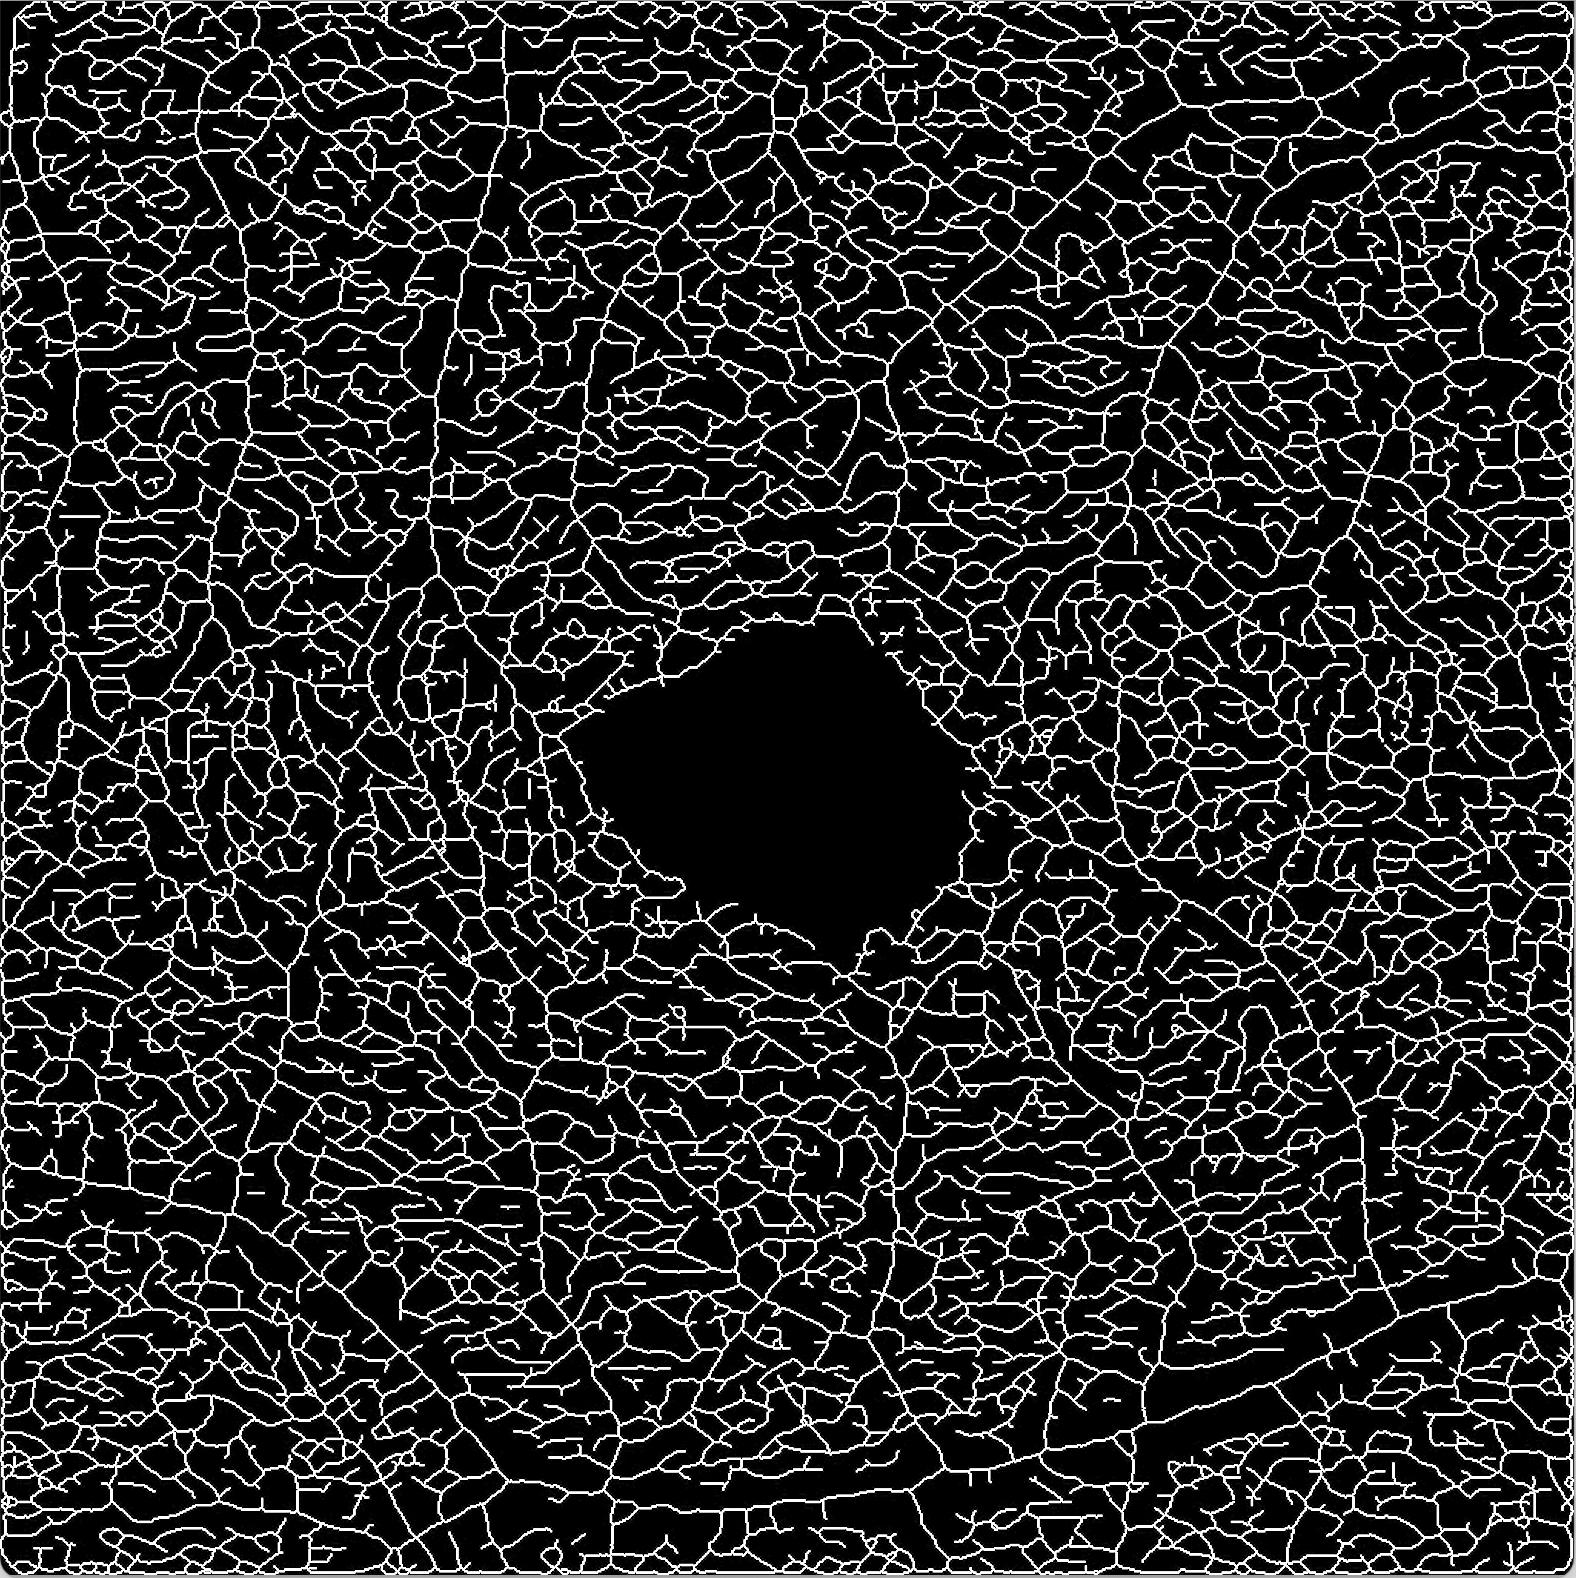

Our image segmentation is divided into three subtasks: the identification of small and big vessel and the FAZ. The final result, see Figure 2(b), is obtained by uniting the binary images with the small and big vessels and subsequently using the FAZ segmentation as a mask that excludes that area.

Refer to caption

(a) Original image

(b) Final segmentation

Figure 2: The combined substeps described in Sections 2.1 and 2.2 yield the final image.

The visual results of the segmentation are very good: small vessels are identified accurately, branches are preserved and the ratio of the vessel diameter is pictured realistically. Furthermore, small non-perfusion areas around larger vessel and vascular angles are also depicted truthfully. See Figure 4 for a visualisation of some details.